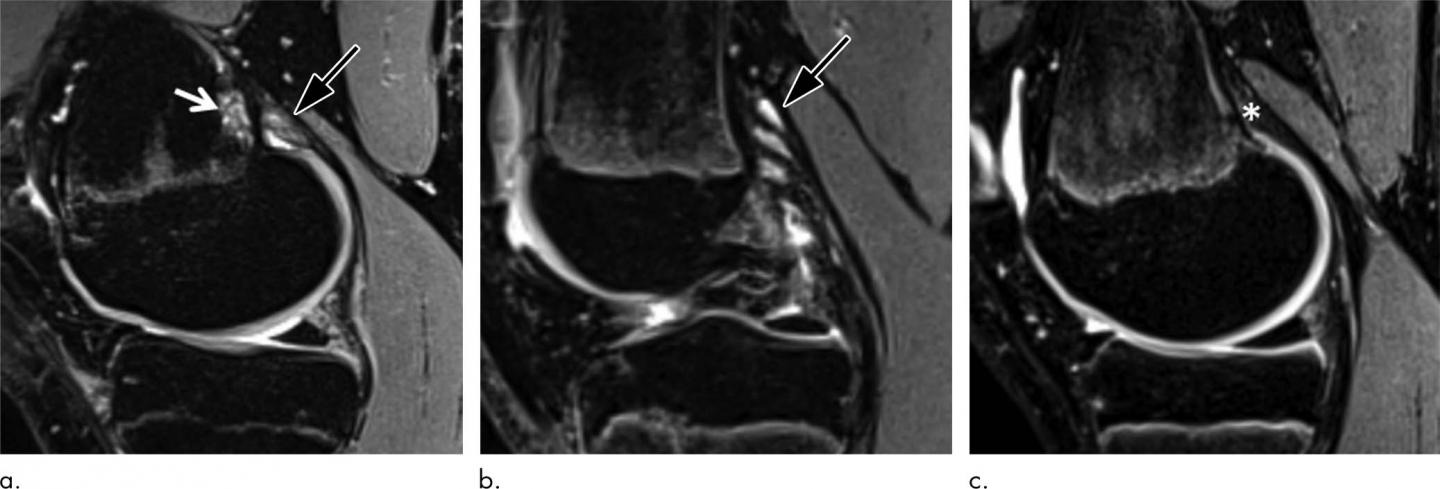

Routine knee MRI of adolescents often reveals tumor-like irregularities in the bone of the distal femur, the part of the thigh bone right above the knee. These irregularities affect the cortical bone, the dense outer surface of the bone. For that reason, they are referred to as distal femoral cortical irregularities (DFCI). DFCI often lead to diagnostic uncertainty because they can be confused with more serious conditions like cancer or infection.

With an increasing number of MRI examinations performed in young patients, DFCI detection is likely to increase, as MRI has a higher sensitivity for detecting lesions than X-rays do, according to study lead author Christoph Stern, M.D., a musculoskeletal radiologist at Balgrist University Hospital in Zürich, Switzerland.

"DFCI are benign lesions, and occurrence around the knee joint is associated with repetitive mechanical stress to the attachment sites of tendons into bone," Dr. Stern said. "DFCI should not be mistaken for malignancy and are not associated with intraarticular damage."

The most common theory behind the DFCI occurrence is that of a "tug lesion" as a result of repetitive mechanical stress where the tendons attach to the bone.

"According to histologic results of DFCI, which have identified a reactive process, we assume there must be increased bone remodeling with resorption and fibrous proliferation at the site of the tendon attachment that is pronounced in young competitive athletes," Dr. Stern said.

The researchers recommend that invasive diagnostic procedures such as biopsies be avoided in these patients due to the benign, usually asymptomatic, and over time self-limiting character of typical DFCIs at the attachment sites of tendons. However, follow-up with MRI might be justified, they said, especially in the rare case where the DFCI causes pain and other symptoms.